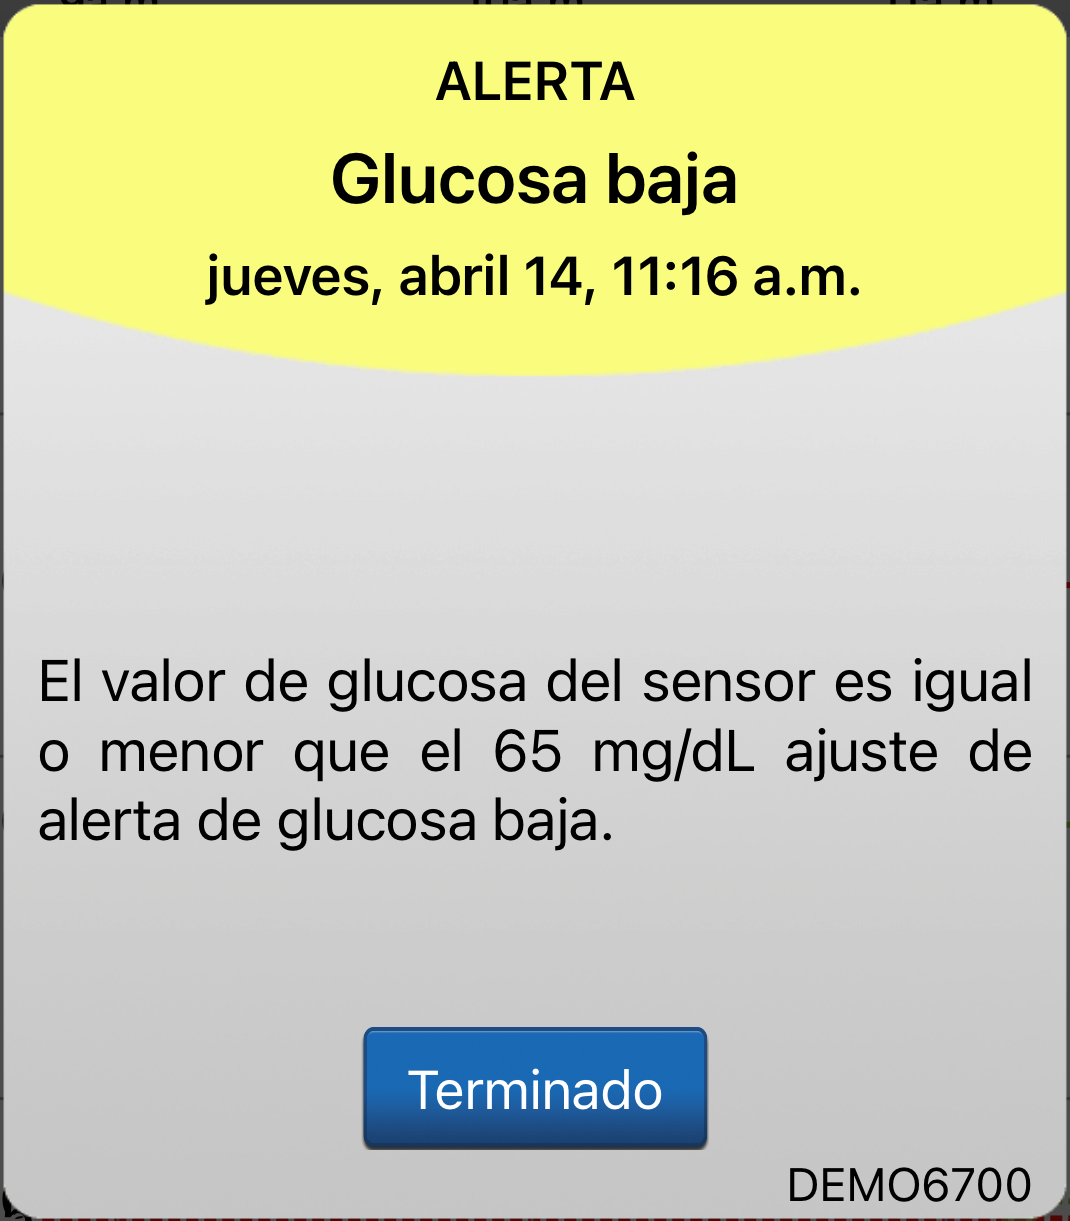

El sistema de MCG le enviará alertas y notificaciones basándose en el estado del sistema y su configuración de glucosa personalizada.

Y, con el sistema de MCG Eversense® E3. no solo verá y escuchará alertas y notificaciones desde la aplicación para móvil, sino que también las sentirá mediante vibraciones únicas sobre el cuerpo desde el transmisor inteligente Eversense® E3.

ALERTAS Y NOTIFICACIONES

El sistema de MCG le enviará alertas y notificaciones basándose en el estado del sistema y su configuración de glucosa personalizada.

Por ejemplo, si su glucosa desciende hasta el nivel de la alerta de glucosa baja o por debajo de él, verá el mensaje emergente de la alerta en la aplicación, escuchará un sonido en su dispositivo móvil

y sentirá una vibración de su transmisor inteligente con un patrón único.

Para ver una lista completa de los patrones únicos de vibración, consulte la Guía del usuario de Eversense® E3.